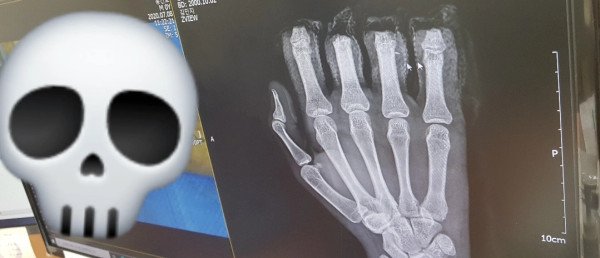

( 21년 6월에입문 ~ 현재 ) 2022년 9월 3일 새벽 1시에 드디어 임페리얼에 도착했습니다. 여러분도 아시겠지만 저는 손이 많이 불편한상황입니다. 2020년6월에 사고로 프레스기에 절단이되버렸는데 10차례의 수

(밑에 사진이 다소 혐짤일수 있으니 조심)